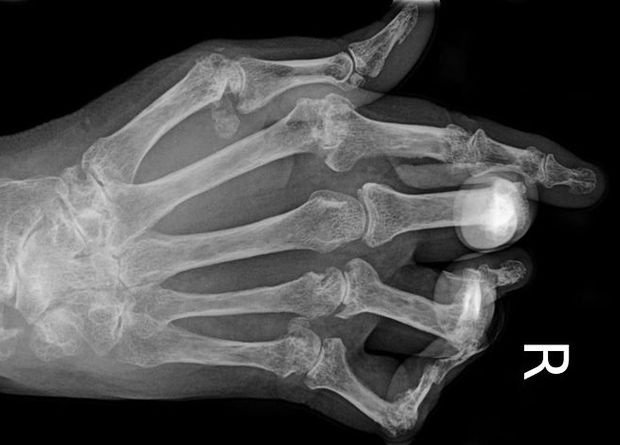

Ревматоидный артрит — это хроническое воспаление, которое вызывает сильные боли и деформирует суставы пациентов. На начальных стадиях они воспаляются «сами по себе» (причина до сих пор не ясна), то есть реакция иммунитета не специфична. Потом после долго воспаления суставная сумка распухает, а иммунные клетки начинают прицельно атаковать и разрушать ткани сустава. Поэтому эта болезнь считается аутоиммунной.